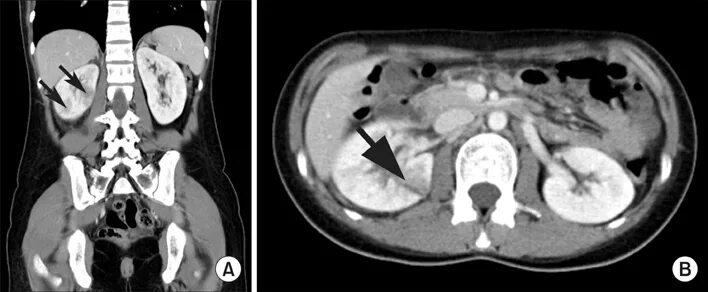

Кт почек с контрастированием как проводится